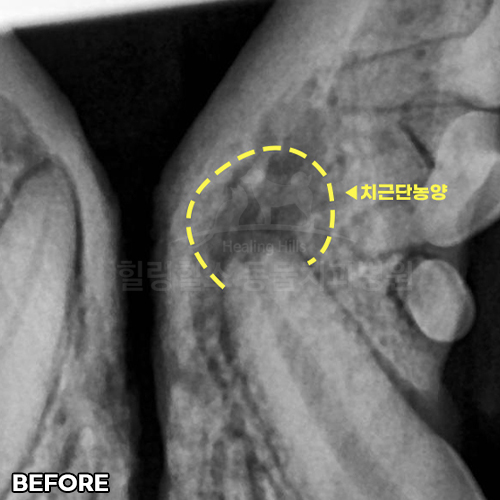

최고 난이도 강아지신경치료 - 꽉막힌 근관&치수괴사! 커다란 반려견치근단농양! 녹아내린 턱뼈! 치통으로 사나워진 모습! 강아지 신경치료 & 치주치료 한달 뒤 좋아졌어요!